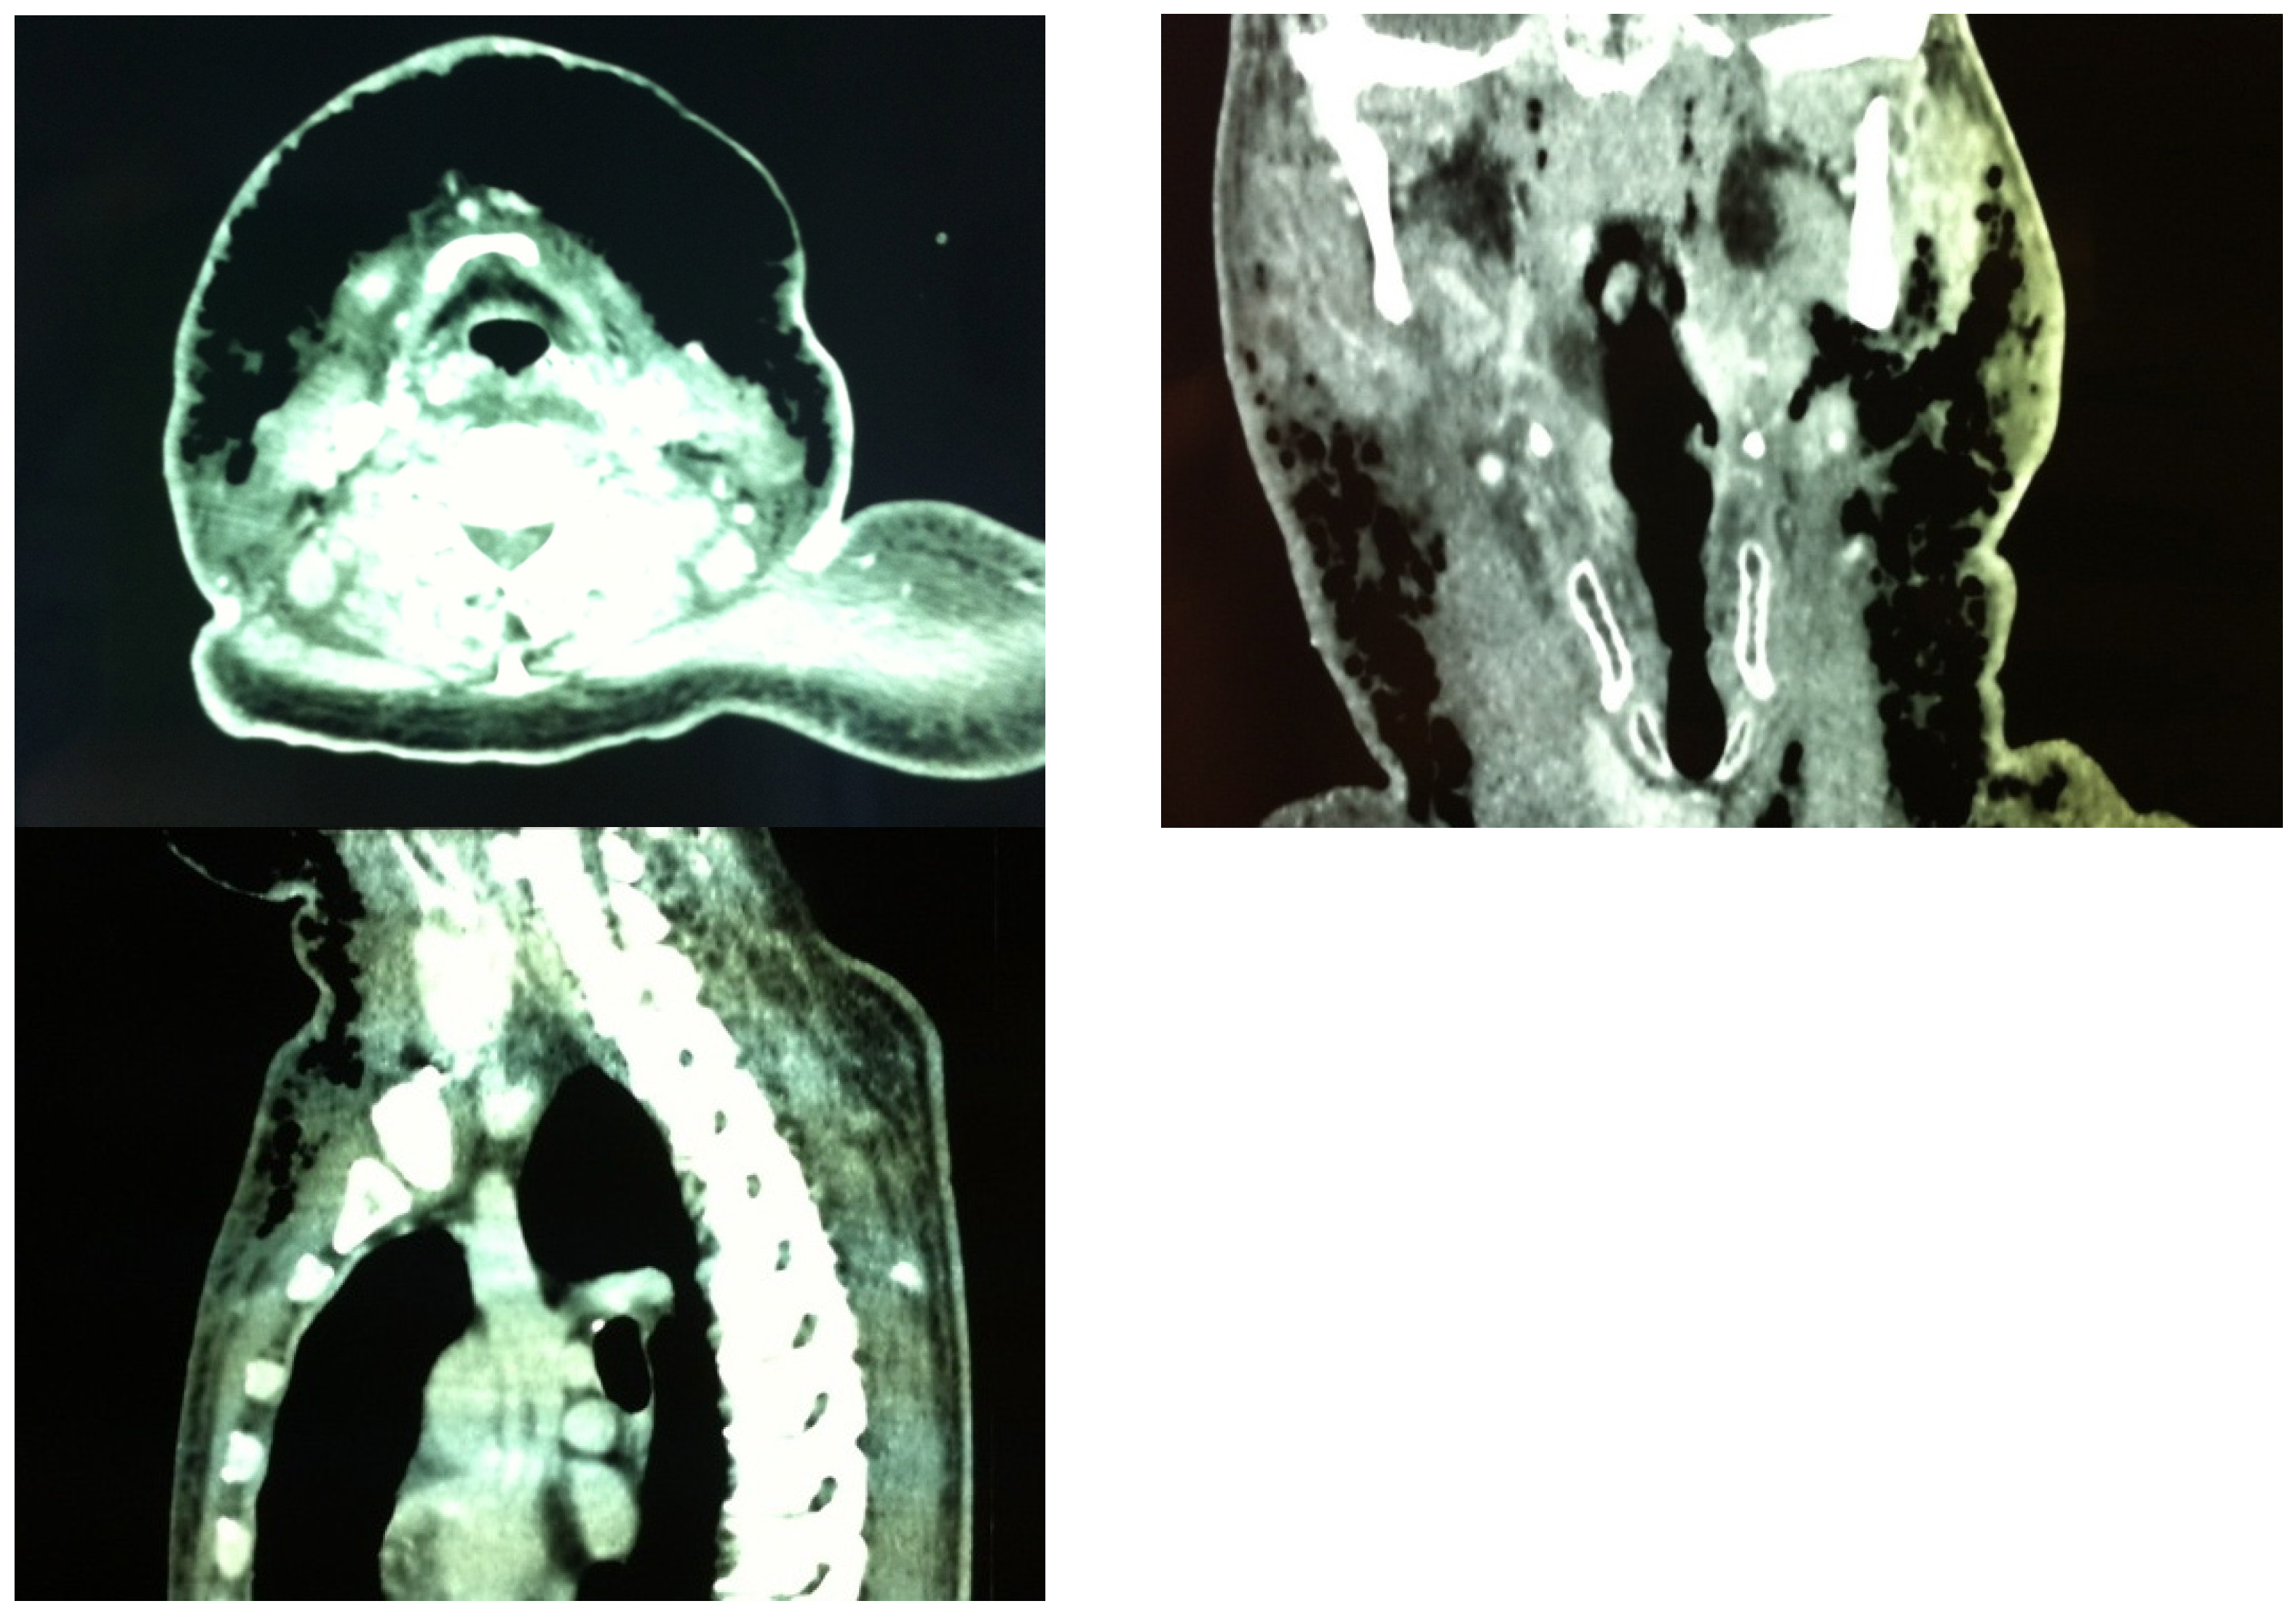

Computed tomography (CT) scan findings include diffuse thickening of the subcutaneous tissue and the cervical fascia, fluid collections in neck compartments, and gas collections. The presence of gas is not a specific sign of necrotizing fasciitis, being present in other musculoskeletal infections [42], and its absence should not exclude the diagnosis if clinically suspected. Gas within fluid collections along subfascial planes is the hallmark of NF [43]. Becker et al. [44] defined the constant diagnostic features found on the CT scans of patients with histologically confirmed NF: (1) cellulitis (diffuse thickening of cutaneous and subcutaneous tissue and reticular enhancement of the subcutaneous fat); (2) fasciitis (thickening and/or enhancement of cervical fascia); (3) myositis (asymmetric thickening or enhancement of cervical muscles); and (4) fluid collections in multiple neck spaces. Gas collections and involvement of the mediastinum were inconstant findings. Involvement of the superficial cervical fascia and thickening and/or enhancement of sternocleidomastoid muscle were present in all patients. A CT scan of our first patient showed abundant and continuous gas collections, descending from the mandibular region to the upper portion of the anterior thoracic wall (Figure 2). This is in contrast with the Becker et al. [44] findings, where all gas collections were located within fluid collections.

Figure 2.

Patient A. Preoperative CT scan showing abundant gas extending subcutaneously from the upper anterior chest wall and the anterolateral neck bilaterally up to the paramandibular region.